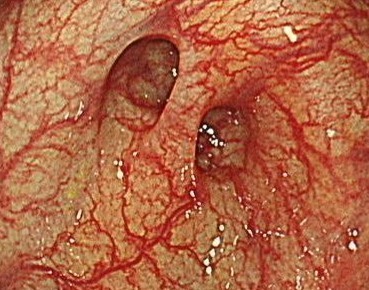

大腸憩室

憩室は大腸の壁にくぼみがある状態で、個人差がありますが年齢とともに増える傾向があります。憩室には便の塊が詰まって周囲に炎症を起こすことがあり、急性の憩室炎や慢性的な腹痛の原因となることがあります。また時に憩室から出血を起こし、下血の原因ともなります。